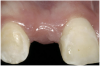

Figure 9  Completed prosthetics (2 years).

Figure 9